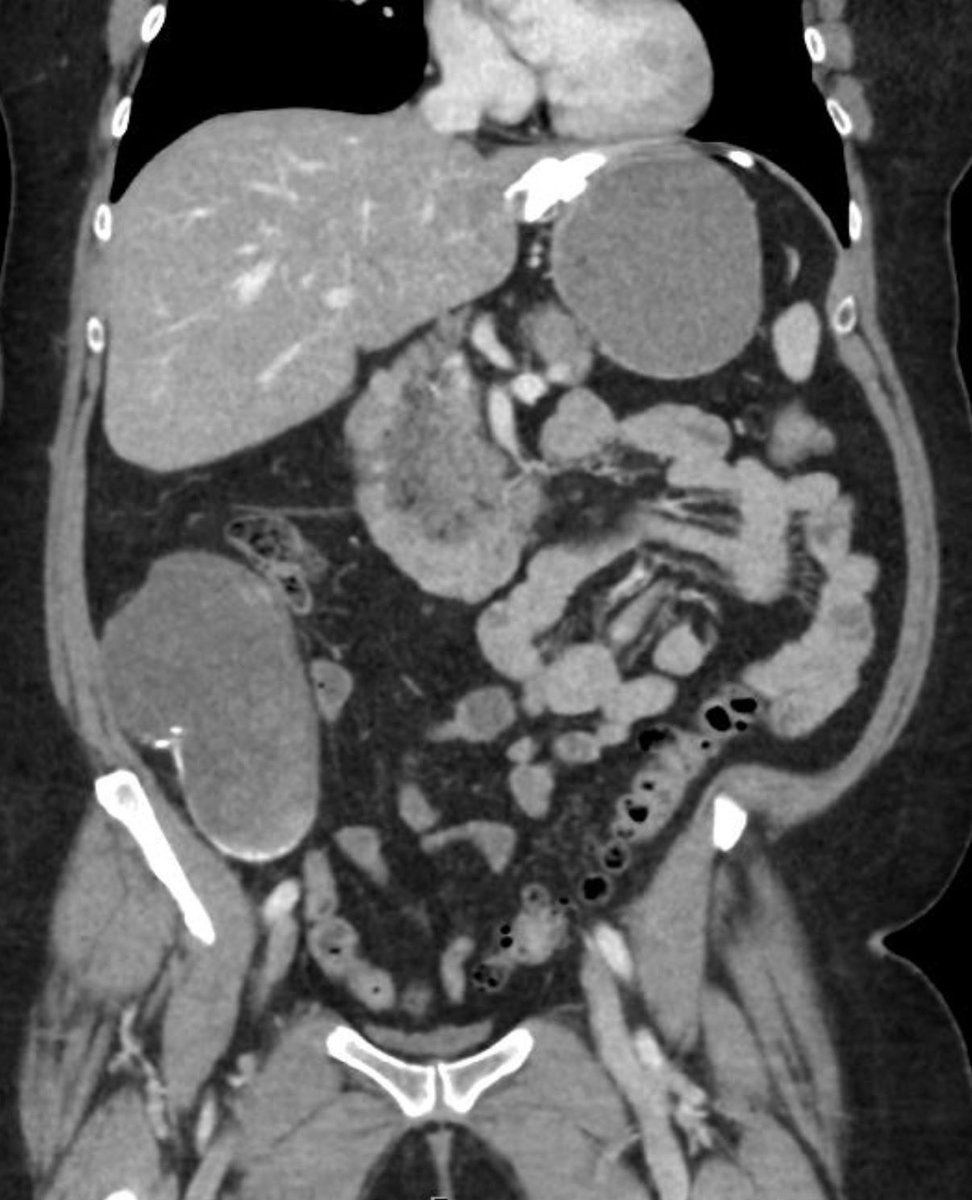

Unique cases from the @RadioGraphics Editor's @cookyscan1 teaching file, including donated cases from her trainees. #CookyBites for companion cases.